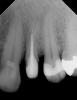

Restorative failure of an existing amalgam restoration on the maxillary left first premolar from recurrent caries is documented here (Figure 2). The periapical radiograph revealed an extensive carious lesion extending into the pulp chamber. After clinical and radiographic evaluation, a treatment plan was discussed with the patient that included endodontic therapy, crown lengthening, and reinforcing the root and supporting the tooth-restorative complex with a fiber-reinforced post and core system.

Fig 2. Restorative failure of an existing amalgam restoration on the maxillary left first premolar from recurrent caries.

Figure 2